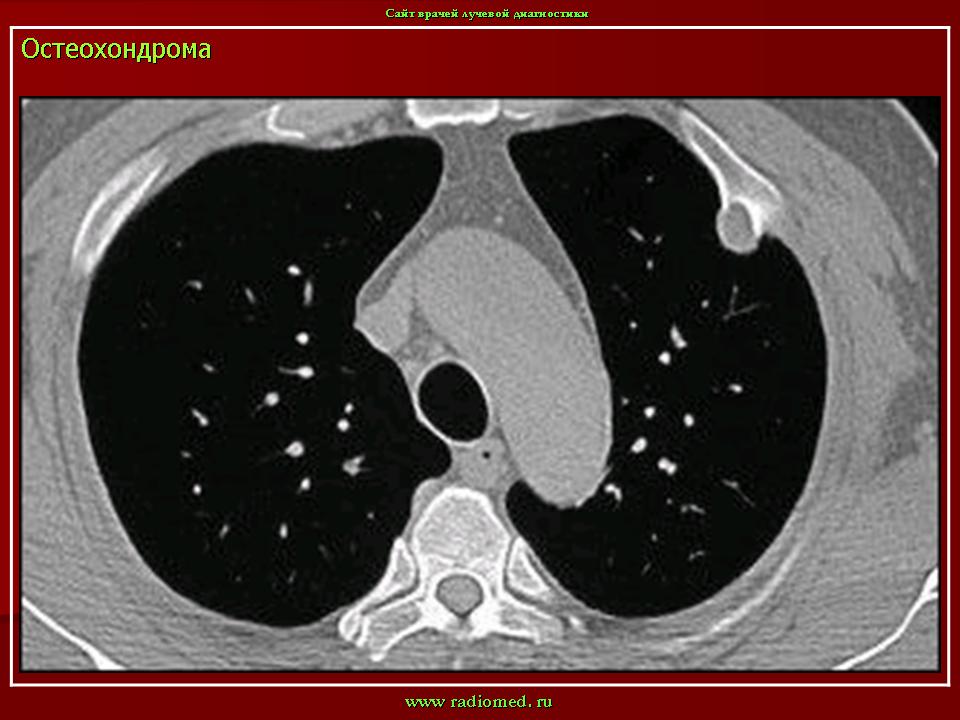

Остеохондрома (костно-хрящевой экзостоз).

Остеохондрома.